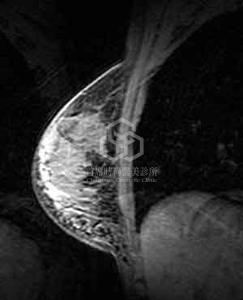

核磁共振攝影(MRI)

時代在進步, 但是仍就有人在開倒車, 即使是目前教育普及, 依然有人接受了[乳房小針美容], 也就是注射silicon矽膠到乳房裏. 而且打針注射的方式一定都是整個乳房亂打, 東打一點, 西打一點, 乳房要豐滿, 打的量又非常大, 真的是非常恐怖. 誇張的是, 這位小姐才24歲, 1年前在台南的美容院施打, 如此青春年華, 因為一個錯誤的決定而毀. 上圖, 可見較白顯影劑的區域是"矽膠與其造成的炎性發炎組織", 幾乎整個乳房都是, 雖然不會演變成癌症, 但是要拿掉就得掏空乳房, 畢竟正常與不正常已經混在一塊, 付出的代價實在可怕!!

請各位網友千萬不要重蹈覆轍, 並與站長共同譴責這種違法害人的行為!!